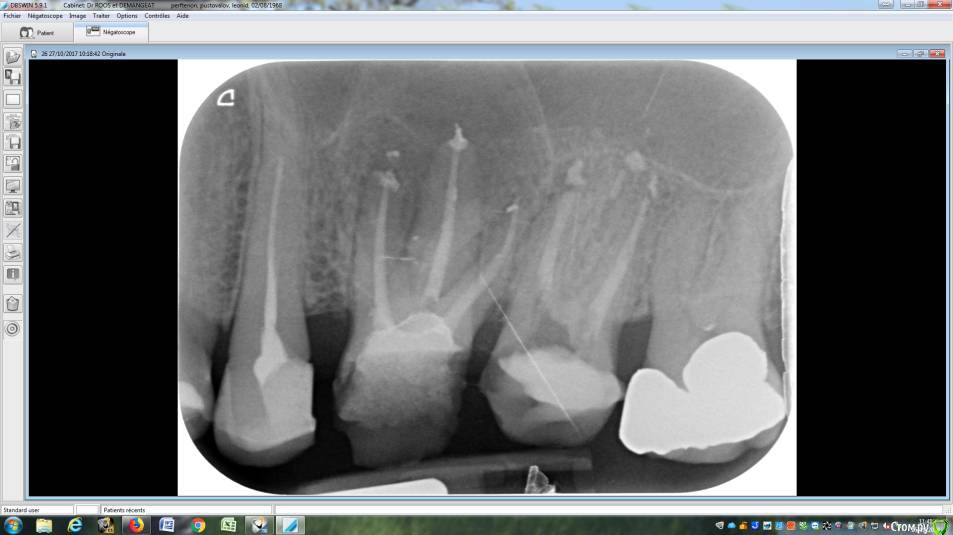

LeoRuss Опубликовано 20 февраля, 2018 Поделиться Опубликовано 20 февраля, 2018 (изменено) Здравствуйте уважаемые метры, в очередной раз обращаюсь к вам за советом.Чуть меньше года назад эндодонтическим методом в полном соответствии с вашими рекомендациями была пролечена киста 26.( http://forum.stom.ru/topic/34508-podsadka-kosti-pri-kiste-nuzhna-li-v-dannom-slucha/ ) При вскрытии зуба выявилась неприятная картина: оба титановых штифта в далеком ‘94м были завернуты мимо корневых каналов прямо в челюсть ;(Док все демонтировал, прочистил под микроскопом и каналы и дыры от штифтов и замуровал МТА : спустя 8 месяцев - 10/2017 : И вроде бы все чудесно, но пару раз за это время десна вокруг зуба воспалялась, и зуб становился более подвижным, но все проходило после 2-3-5 дневного интенсивного полоскания хлоргексидином. Три недели назад была наконец то установлена коронка на соседний 27й, десна с внутренней стороны 26ки тогда была тоже припухшей и протезист посоветовал сходить на контроль к эндодонтисту. Напросился и сходил через неделю, десна за это время еще чуть распухла (только со стороны языка), стало больно при легком нажатии на десну в районе верхушки корня ближнего к 25ке и при покачивании зуба. Док сделал снимок, сказал что все чисто и он понятия не имеет почему все надулось. Вариант удаления забраковал, сказал что по его мнению все хорошо, и можно уже ставить коронку. А вот в импланте смысла никакого, тем более что кости для него пока недостаточно, тк межкорневая область еще не дозаросла. Посоветовал терпеть и.. поставить коронку, тк нагрузка на зуб при жевании должна активировать заживление.Но жевать на этой стороне я стал почти месяц назад, сразу после установки временной коронки на 27, вот с тех пор с 26кой все хуже и хуже. За последние полнедели опухоль сильно увеличилась, и между 25/26, и в сторону нёба, дергает в ритме пульса. Появились отголоски боли в носоглотке и в заглазье.Терпеть уже плохо получается, да и смысла не вижу. Вижу два варианта:1. Удалять 26 чтоб не мучаться, с последующей имплантацией, но как быть с нехваткой кости?2. Вскрыть каналы и прочистить еще раз, но даст ли это хоть что то, да и возможно ли в принципе? В любом случае хотел бы узнать ваше мнение, спасибо ! Изменено 20 февраля, 2018 пользователем LeoRuss Ссылка на комментарий